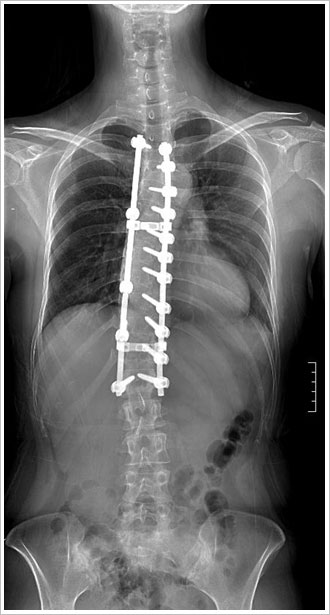

¼ö¼úÀû Ä¡·á

- ¼ºÀå±âÀÇ

45µµ ÀÌ»óÀÇ ¸¸°î

- ¼ºÀåÀÌ ³¡³ 50µµ ÀÌ»óÀÇ ¸¸°î

* ¼ö¼ú¹ý

- ÈĹ汳Á¤ ¹× ÈĹæ±â±â¼ú : ôÃß°æ ³ª»ç¸ø

°íÁ¤¼ú

- Àü¹æ±³Á¤ ¹× Àü¹æ±â±â¼ú : ÃÖ¼ÒÀý°³¹æ½Ä,

³»½Ã°æ ¹æ¹ý

- ÀüÈĹ汳Á¤ ¹× ÈĹæ±â±â¼ú

- °ßÀÎ ÈÄ ÈĹ汳Á¤¼ú

- Èä°û¼ºÇü¼ú

û¼Ò³â±â Ư¹ß¼º ôÃßÃø¸¸Áõ : 20¼¼/¿©ÀÚ